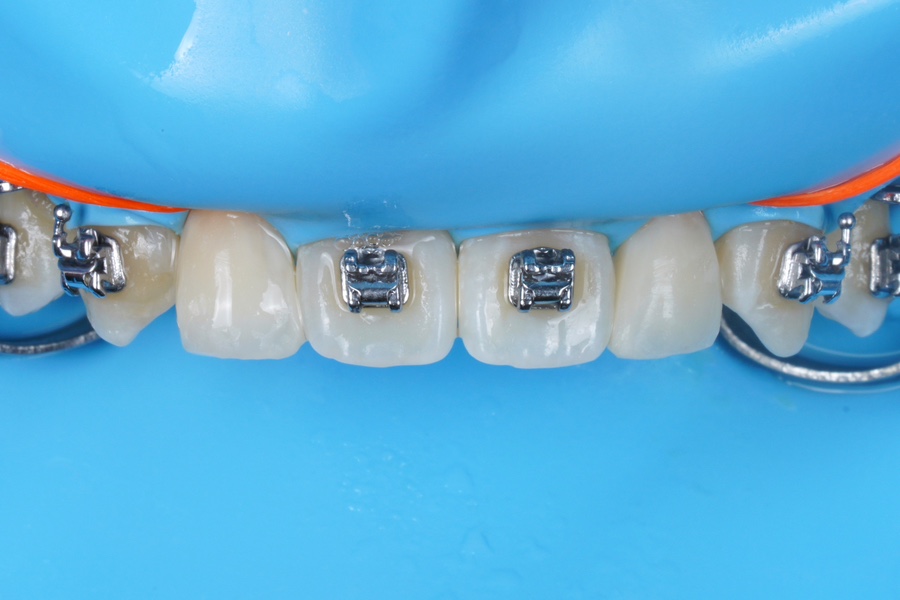

레진 비니어 완료

Direct Composite Veneer

완료 사진입니다.

순수 시술 시간은 1시간 10분!

저희 치과 왜소치 레진 비니어 접착 후

바로 교정치과에 가서

나머지 교정기도 다 떼셨어요.

교정치과에서도

자연스럽게 잘 됐다고

이야기 들으셨다고 하네요 ㅎㅎ

투명층을 왜 굳이 만들어 줘야할까요?!

잇몸에서부터 씹는면까지

자연치아가 가지는 고유의 그라데이션

그 색상변화가

치아를 자연스러워 보이게 하고

살아있게 만드는 거라고 생각해요.